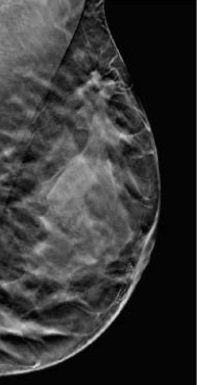

La Tomosintesi eseguita con i mammografi Hologic aiuta a individuare i tumori invasivi per una diagnosi precoce e a ridurre il numero di richiami non necessari. Semplicemente, è una mammografia più accurata

Un mammografo diverso da qualsiasi altro

Il Selenia Dimensions è un mammografo versatile progettato per offrire una tecnica di Tomosintesi rivoluzionaria. Si è osservato che la Tomosintesi Hologic in combinazione con la mammografia 2D riduce considerevolmente il numero dei falsi positivi 1,7 , migliorando l'efficienza e riducendo i costi di gestione 14-15.